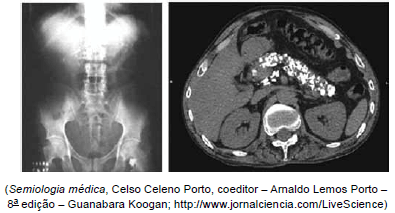

Homem de 64 anos procurou Pronto-Socorro por queixa de dor abdominal em pontada, de forte intensidade, há 4 dias, com início em localização epigástrica e irradiação em faixa para hipocôndrios, flancos e região dorsal. A dor era acompanhada de vários episódios de vômitos e evacuações fétidas e amareladas, com gotículas de gordura. Negou febre ou icterícia. Etilista crônico desde 12 anos de idade. O médico de plantão solicitou RX simples e tomografia de abdome, demonstrados a seguir.

Com base no enunciado e nas imagens, é correto afirmar que a etiopatogenia da lesão demostrada é: